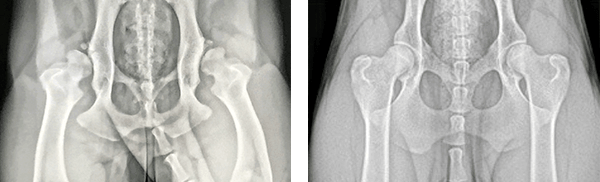

Sampson is a 3-year-old Rottweiler who presented to an OrthoPets Partner Clinic for right hind limb lameness. He was diagnosed with a right cranial cruciate ligament tear and severe hip dysplasia. When surgery isn't an option due to age, health, financial, or other reasons, OrthoPets can offer an alternative solution via a custom-made orthosis.